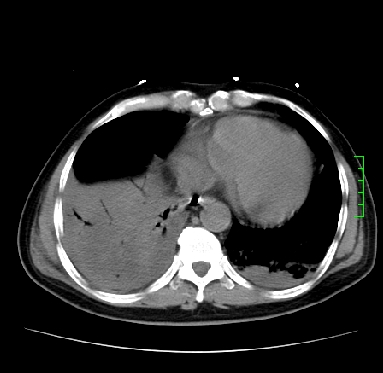

11号ct

双肺感染性病变,下叶膨胀不全,胸水,左室大。

1)两肺感染性病变(右肺下叶肺脓肿可能)。2)双侧胸腔积液,以右侧为甚。

ards,肺感染性病变,右下叶实变,双侧胸腔积液,右侧为著,叶间胸膜积液,右上肺陈旧性tb纤维灶,左室大。